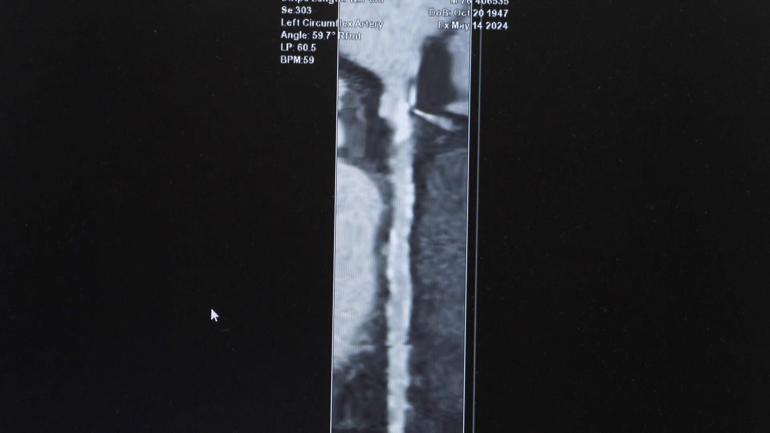

‘TOMOGRAFİK ANJİYOGRAFİ İLE 35 YAŞ ÜSTÜ ANİ ÖLÜMLERİ ÖNGÖRMEK MÜMKÜN’

Son yıllarda koroner tomografik anjiyografinin, belirli risk gruplarında kalp damar sağlığının daha ayrıntılı değerlendirilmesinde dünyada da önemli bir seçenek haline geldiğini anlatan Prof. Dr. Özveren, şu ifadeleri kullandı:

“Hipertansiyonu, diyabeti olan, sigara içen ya da ailesinde erken yaşta kalp krizi öyküsü bulunan kişilerde; damar tıkanıklığı ya da darlıkları gibi hayati risk oluşturabilecek sorunlar tomografik anjiyografi ile yüksek doğrulukla tespit edilebiliyor. Bu nedenle risk grubundaki kişilere, örneğin 5-10 yılda bir tomografik anjiyo ile değerlendirme yaptırmalarını öneriyoruz. Ancak bu yöntemin herkes için rutin bir tarama aracı olarak görülmemesi, sadece gerekli durumlarda ve hekimin önerisiyle yapılması gerekir.”